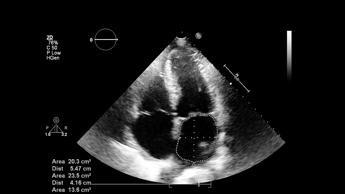

(Adnkronos) – Per la prima volta in Europa, 3 società scientifiche italiane hanno realizzato un documento pionieristico sull'ultrasonografia polmonare (Lus) nei pazienti critici, coprendo l'intero arco della vita. La 'buona pratica clinica', pubblicata il 4 novembre, nasce dalla sinergia tra la Società italiana di anestesia, analgesia, rianimazione e terapia intensiva (Siaarti), la Società italiana di radiologia medica e interventistica (Sirm) e la Società italiana di neonatologia (Sin). "Questo documento rappresenta un esempio virtuoso di collaborazione tra diverse specialità mediche – evidenzia Elena Bignami, presidente Siaarti – L'approccio innovativo adottato ottimizza l'utilizzo dell'ecografia polmonare per tutti i pazienti critici, indipendentemente dalla loro età e patologia. E' significativo come buona parte della letteratura scientifica analizzata sia di provenienza italiana, confermando il nostro Paese come front runner nel campo della ultrasonografia polmonare nel paziente critico". La rilevanza del documento emerge anche dalle parole di Giorgio Conti, Editor-in-Chief della rivista 'Jaacc' di Siaarti: "Questo documento intersocietario segna un punto di svolta nella collaborazione fra specialità mediche. Il dialogo tra anestesisti-rianimatori, radiologi, pediatri e neonatologi ha prodotto uno strumento unico, tracciando una strada innovativa da seguire anche in altri ambiti". La pubblicazione del documento – riporta una nota – sancisce un dato di fatto: l'ecografia polmonare si sta rivelando uno strumento prezioso nella pratica clinica quotidiana. "Si tratta di un documento che sottolinea l'importanza dell'ultrasonografia polmonare per migliorare la gestione clinica in ambiente ospedaliero – spiega il presidente Sirm, Andrea Giovagnoni – La Lus può ottimizzare i percorsi diagnostici, riducendo l'uso di tecniche invasive o radiologiche più costose e rischiose". Il testo "rappresenta uno strumento prezioso per decisioni cliniche rapide nelle emergenze, con l'obiettivo prioritario di salvaguardare sempre la sicurezza del paziente". "L'ecografia polmonare è una tecnica che permette di valutare le più comuni patologie polmonari tipiche dei neonati nati anche prima del termine – illustra il presidente Sin, Massimo Agosti – Consente al neonatologo di integrare il quadro clinico dei neonati critici con una metodica diagnostica efficace, rapida e facilmente riproducibile, atta ad assistere i medici nella gestione di patologie spesso rapidamente progressive e tempo dipendenti. Possiede un'alta accuratezza diagnostica, non utilizza radiazioni ionizzanti ed è facilmente adattabile al contesto della Terapia intensiva neonatale poiché eseguita dai neonatologi direttamente al letto del paziente. Pertanto, visti i suoi numerosi vantaggi, negli ultimi anni si è affermata come un insostituibile alleato in ambito neonatologico". Il documento – descrive la nota – fornisce indicazioni standardizzate per l'esecuzione degli esami ecografici, promuove la formazione continua degli operatori e definisce percorsi diagnostici basati sulle più recenti evidenze scientifiche, rappresentando un riferimento fondamentale per il miglioramento della pratica clinica in Italia. "L'ecografia polmonare riduce i rischi per il paziente e accorcia i tempi diagnostici, aumentando la precisione e l'efficacia delle cure, soprattutto nei casi di emergenza", rimarcano gli esperti. Grazie a questo documento, l'Italia si pone all'avanguardia in Europa per l'uso clinico di questa tecnica, offrendo uno standard di cura innovativo e di alta qualità. —salutewebinfo@adnkronos.com (Web Info)